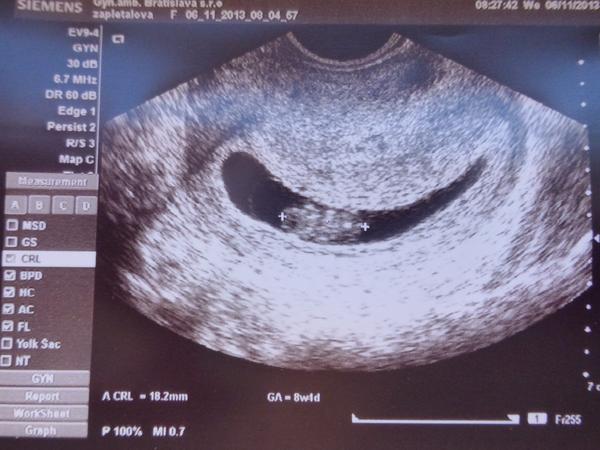

@mabe to vlavo vyzera ako hlava, ze?🙂

@mabe ale nehybalo sa to, ci to sa este nema hybat?srdiecko ale bilo a to je hlavne🙂

@nefertitka ještě není tak aktivni, aby si videla v takove chvilce pohyby, neboj. dulezity je, ze roste, srdicko tluce 😉

@mabe no ved ano🙂 ale podla ms som uz 10tt a podla sona iba 9tt...zas to bude taky drobec ako Niki🙂